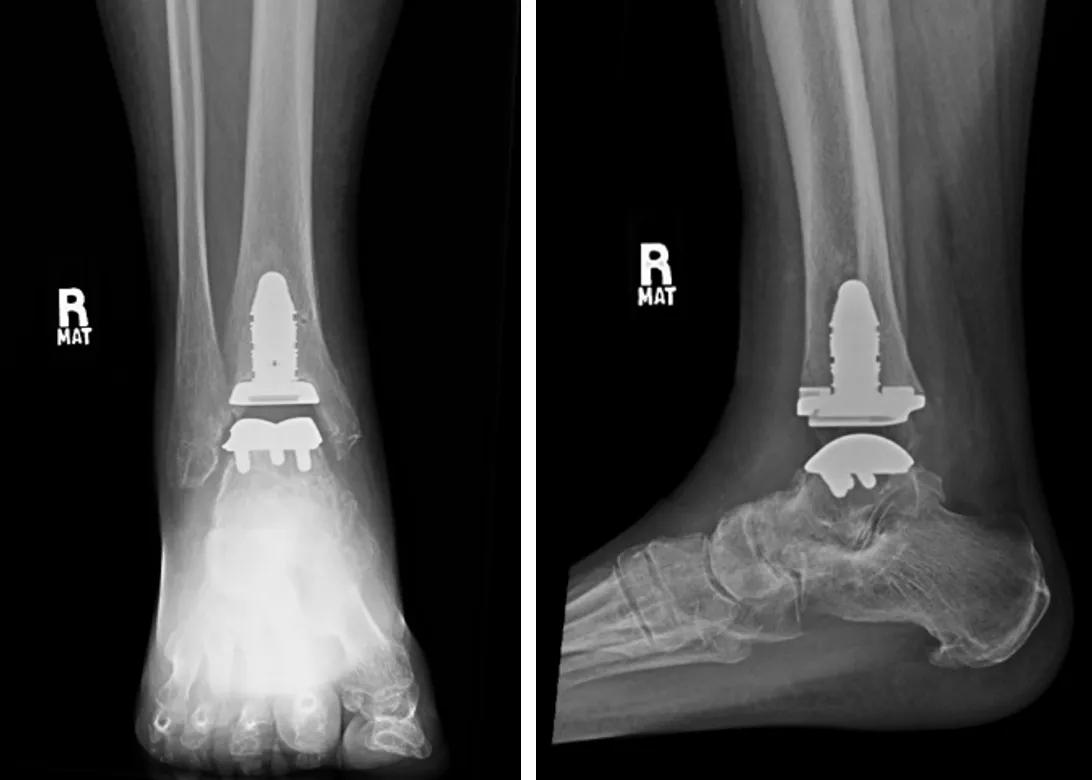

Stemmed total ankle replacement

Nonstemmed total ankle replacement